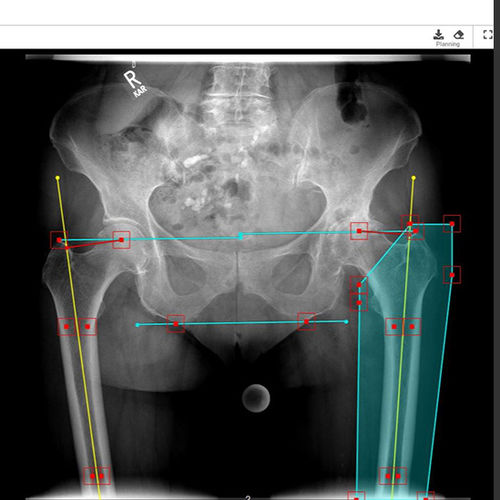

Planification automatique :

Après avoir choisi le côté du corps, les points de repère suivants s’affichent automatiquement :

• Ligne de référence

• Différence de longueur des jambes

• Axe de la diaphyse fémorale gauche/droite

• Trochanter majeur gauche/droite

• Centre de l’articulation de la hanche gauche/droite

• Découpe du fémur

• Décalage fémoral

Les points reconnus peuvent être ajustés manuellement si nécessaire. Après confirmation des points de repère, les cotyles et les tiges peuvent être insérées directement. mediCAD® Web offre avec ce module une planification préopératoire endoprothétique très rapide et efficace.